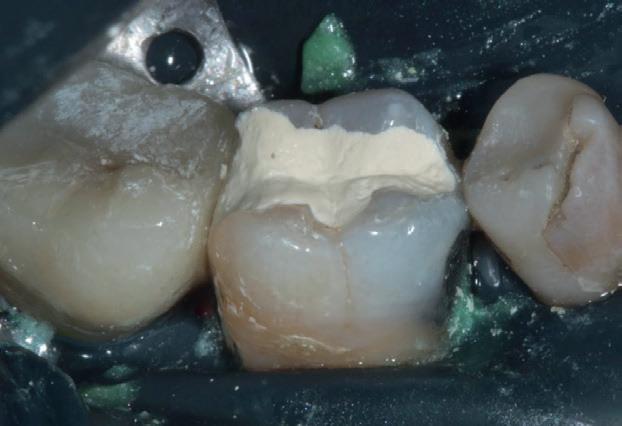

izolarea cu digă de cauciuc, restaurarea din amalgam a fost îndepărtată complet și s-a obținut accesul la cavitatea carioasă (fig. 3-5). În ciuda proximității față de țesutul pulpar, nu a avut loc nicio expunere, iar cavitatea de clasa a II-a a fost restaurată complet cu Biodentine™ (fig. 6-8).

La controlul de două luni, nu au fost raportate simptome, nu s-a obiectivat radiologic nicio leziune periapicală, iar examenul clinic a

demonstrat o vitalitate în limite normale (fig. 9-10). Prin urmare, s-a decis efectuarea restaurării definitive, păstrând Biodentine™ ca bază definitivă.

Materialul Biodentine™ a fost parțial îndepărtat și peste acesta s-a plasat o obturație din compozit (fig. 11). S-a efectuat o gravare selectivă a smalțului, urmată de aplicarea unui sistem adeziv (Palfique Bond®, Tokuyama) (fig. 12-13). După foto-

polimerizare, s-a fixat sistemul de matrice (SeptoMatrix, Septodont) și s-a utilizat o matrice mare cu un inel moale pentru un contur mai bun și un punct de contact proximal (fig. 14). Restaurarea a fost începută în porțiunea distală, transformând cavitatea de clasa a II-a într-o cavitate de clasa I (fig. 15). În final, suprafața ocluzală a fost restaurată folosind compozitul Palfique LX5® (Tokuyama) (fig. 16). După fotopolimerizare, s-a aplicat gel de glicerină pentru a permite o mai bună fotoactivare a stratului superficial. Restaurarea a fost apoi finisată și lustruită, înainte de îndepărtarea digii de cauciuc și verificarea ocluziei (fig. 17).

Figurile:

6. Biodentine™ aplicat prin procedura

Bio Bulk-Fill. 7. Situația clinică după 12 minute și îndepărtarea matricii.

8. Situația clinică după îndepărtarea digii de cauciuc. 9. Radiografia de control la 2 luni postoperator.